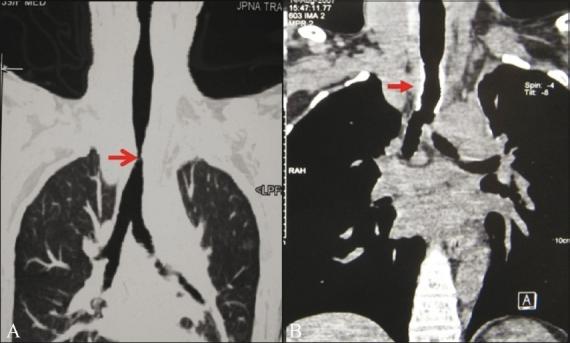

Fifty-six patients were selected for analysis based on the detection of major airway lesions on fiber-optic bronchoscopy (FB) or routine axial images. Comparisons were made between axial images, virtual bronchoscopy (VB), minimal-intensity projection (minIP), and multiplanar reformatted (MPR) images using FB as the gold standard. Lesions were evaluated in terms of degree of airway narrowing, distance from carina, length of the narrowed segment and visualization of airway distal to the lesion.

MPR images had the highest degree of agreement with FB (Κ = 0.76) in the depiction of degree of narrowing. minIP had the least degree of agreement with FB (Κ = 0.51) in this regard. The distal visualization was best on MPR images (84.2%), followed by axial images (80.7%), whereas FB could visualize the lesions only in 45.4% of the cases. VB had the best agreement with FB in assessing the segment length (Κ = 0.62). Overall there were no statistically significant differences in the measurement of the distance from the carina in the axial, minIP, and MPR images. MPR images had the highest overall degree of confidence, namely, 70.17% (n = 40).

Three-dimensional reconstruction techniques were found to improve lesion evaluation compared with axial images alone. The technique of MPR images was the most useful for lesion evaluation and provided additional information useful for surgical and airway interventions in tracheobronchial stenosis. minIP was useful in the overall depiction of airway anatomy.

基于纤维支气管镜检查(FB)或常规轴向图像上检测到的大气道病变,选取56例患者进行分析。以FB作为金标准,对轴向图像、虚拟支气管镜检查(VB)、最小密度投影(minIP)和多平面重组(MPR)图像进行比较。从气道狭窄程度、距隆突的距离、狭窄段长度以及病变远端气道的可视化情况等方面对病变进行评估。

在描绘狭窄程度方面,MPR图像与FB的一致性程度最高(Κ = 0.76)。在这方面,minIP与FB的一致性程度最低(Κ = 0.51)。MPR图像上病变远端的可视化效果最佳(84.2%),其次是轴向图像(80.7%),而FB仅能在45.4%的病例中看到病变。在评估节段长度方面,VB与FB的一致性最佳(Κ = 0.62)。总体而言,轴向图像、minIP图像和MPR图像在测量距隆突的距离方面无统计学显著差异。MPR图像的总体置信度最高,为70.17%(n = 40)。

与单纯的轴向图像相比,发现三维重建技术可改善病变评估。MPR图像技术在病变评估中最有用,并为气管支气管狭窄的手术和气道干预提供了额外的有用信息。minIP在气道解剖结构的整体描绘中很有用。